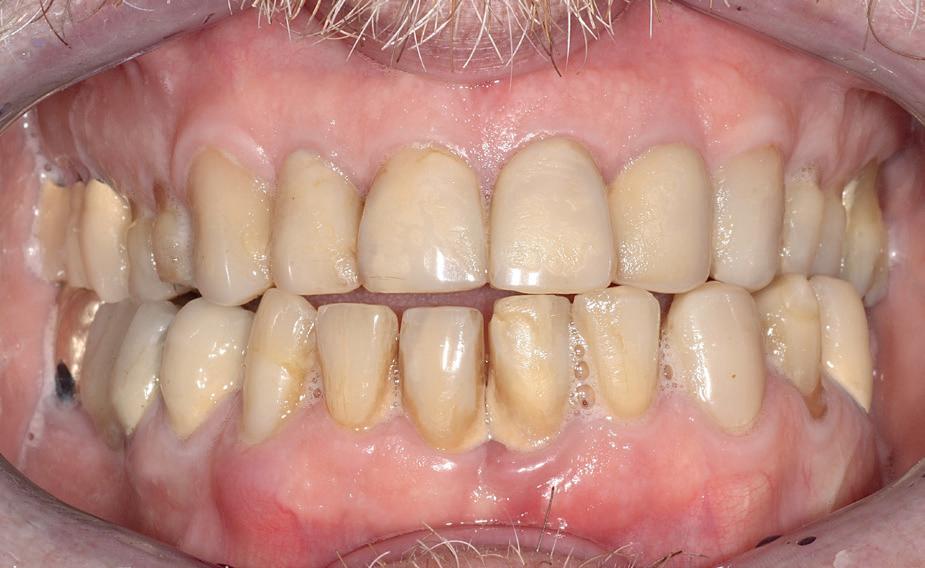

De patiënt, een 70-jarige man, had in het verleden tandheelkundige zorg ontvangen die zich kenmerkte door een ad hoc benadering. Er was geen sprake van een overkoepelend behandelplan of lange termijnvisie. De patiënt had naar eigen zeggen jarenlang niets

aan zijn gebit gedaan behalve pappen en nathouden. Tandheelkundige zorg werd enkel verleend wanneer er zich een probleem voordeed (afbeelding 1, 3, 5).

De patiënt wenste een duurzaam en esthetisch herstel van het gebit, bij voorkeur zonder orthognatische chirurgie of orthodontie.

Na afronding van de eerste twee behandelstappen werd parodontale stabiliteit bereikt, zoals waarneembaar op de parodontiumstatus en (röntgen)foto’s (afbeelding 6, 8). De patiënt toonde aantoonbare verbetering in mondhygiëne (afbeelding 4) en bleef gemotiveerd om de behandeling voort te zetten.